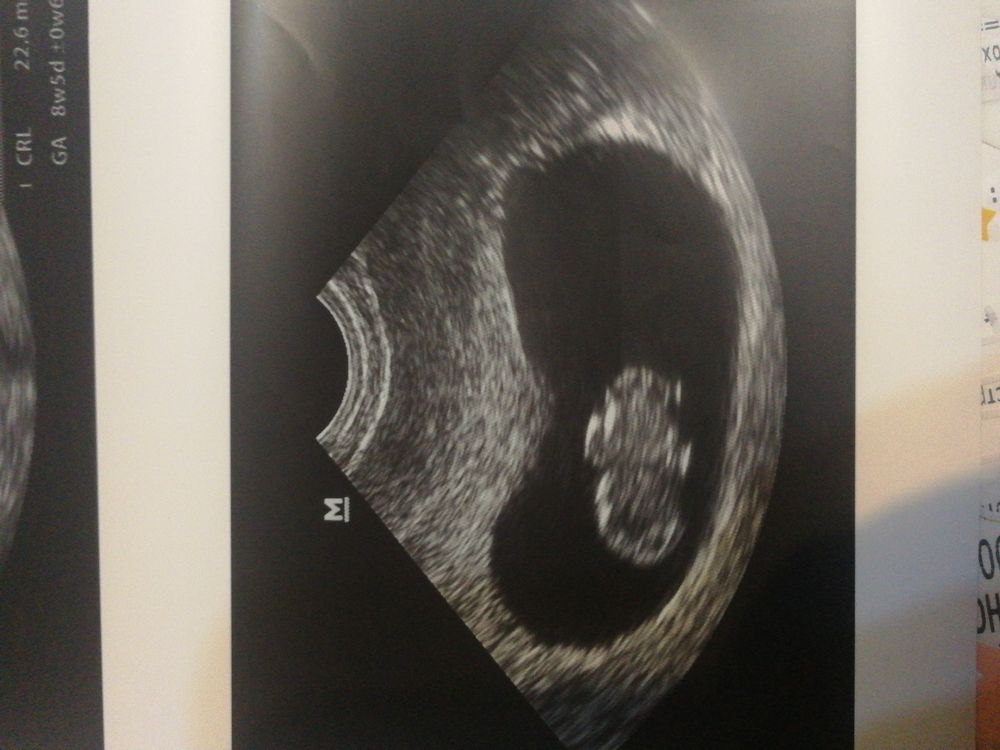

Какой прикольный пупс))) ой жду своё УЗИ в 8 недель, неужели такого человека уже тоже увижу😍 Поздравляю Вас от всей души!

27.08.2021

Victoria Sever, и вам такого же прикольного желаю🤰🤗💕

Классно ему там :) как в бассейне плавает

Большой ЖМ , срок 9+4 недель УЗИ на 20 дпп